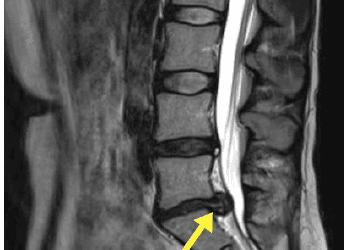

I Must Have Slipped A Disc!

This image is an MRI of a patient’s lumbar spine (lower back), showing a significant disc bulge. You can see the disc...